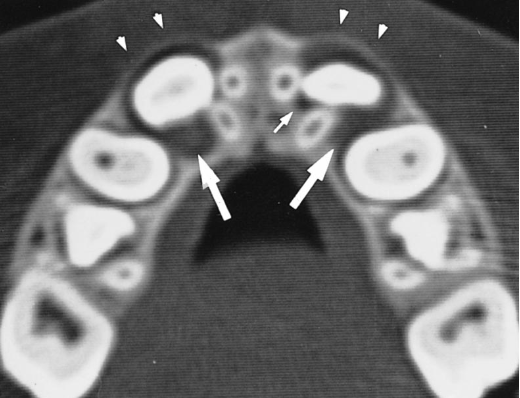

🔍 Follicle Shape & Jaw Bone Structure

📸 CBCT Scans Reveal an Interesting Pattern:

- 🟠 Loosely spongeous bone + spacious jaws → Follicle adapts a spherical shape 🔵

- 🔺 Limited space for expansion → Follicle takes on an irregular shape 🟠

🧐 Surprisingly, this hasn’t been reported before in literature!